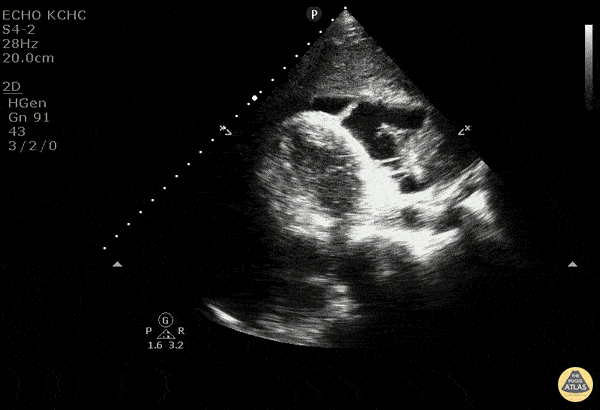

40 y/o F with 2-3 months of weight loss and new diagnosis of mediastinal mass. Sent from clinic for SOB. Patient initially tachycardic, tachypnic. EKG shows electrical alternans. US shows large hypoechoic area with mobile hyperechoic lines in an effusion concerning for fibrinous exudate/growth. There is no sign of end diastolic right ventricular collapse. Findings are consistent with a pericardial effusion with fibrin deposits without evidence of tamponande. For POCUS - the easiest assessment of tamponade is to look at end diastolic right atrial and ventricular collapse. Since the right side of the heart typically is at lower pressures, it will be the first to collapse from the pressure in the pericardium. It is easily measured with m-mode across the wall of the ventricle or atria. Bedside US is an amazing tool and can quickly and effectively show the hemodynamic status in pericardial effusion, so that the correct management can be done. Dr. Carolina Camacho, Taylor Surles, Michael Greisinger, and Scott Kendall - Kings County Emergency Medicine